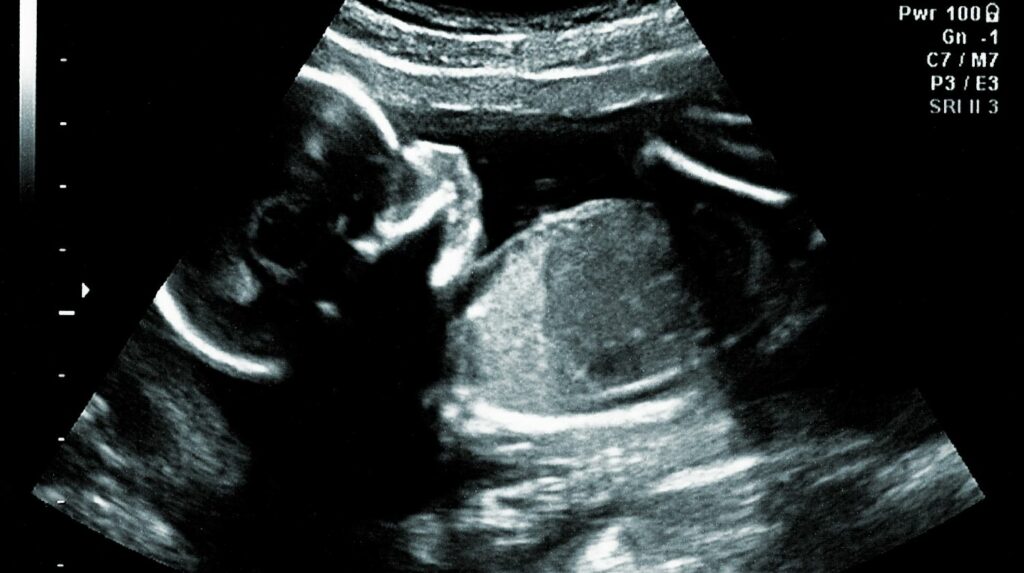

Pored ove podele, svaka krvna grupa je pozitivna ili negativna, u zavisnosti od toga da postoji RH faktor (Rezus faktor) ili ne. RH faktor je važan u trudnoći.

Naime, ukoliko roditelji imaju različit RH faktor, to može biti problem ne u prvoj, već u kasnijim trudnoćama i mora se pratiti.